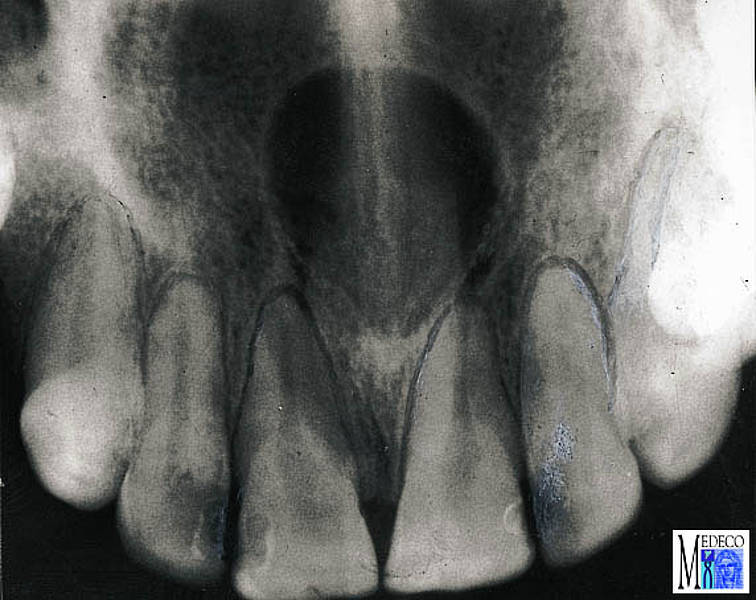

Beschreibe Röntgenbild

Ductus Nasopalatinus- IncisivisKanalZyste ,

gehört der Gruppe dysgenetische nicht odontogene/Fissurale Zysten.

Differentialdiagnostisch könnte auch radikuläre Zyste in Frage kommen, röntgenologisch schwer einschätzbar da fälschlicherweise die Wurzel der Front in die Ductus nasopalatinus Zyste ragen können und die Diagnose radikuläre Zyste sich stellen kann.

Weiter DD’s zu D.Nasopala-´.Z.:

( - Knochemetastase )